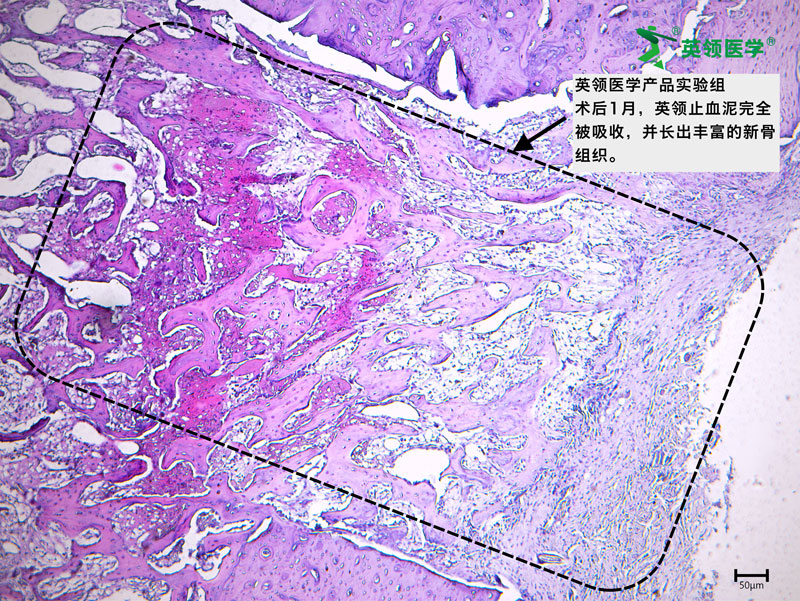

临床试验期间,ABHM表现出优异的临床性能和安全性,其可降解特性与成骨兼容性受到多家临床中心手术专家的强烈赞叹。该产品通过在骨创面实现快速机械封堵,有效控制出血,并可在4周内完全降解,避免传统骨蜡因长期滞留所导致的骨愈合障碍、异物肉芽肿、慢性炎症及感染等并发症,为骨创面止血提供了更安全、更符合生理愈合过程的解决方案。

动物实验